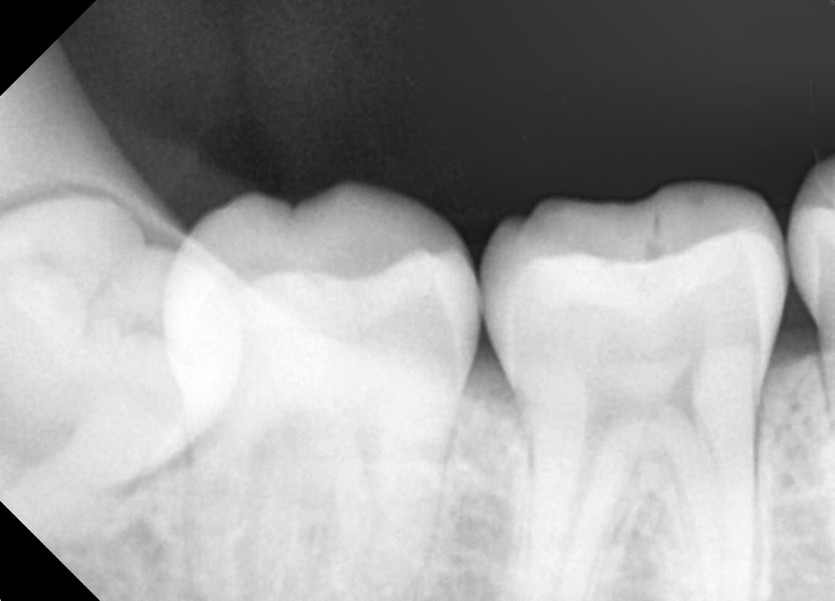

#38,48 사랑니 발치

구강 외과 전문의가 당일 발치했습니다.